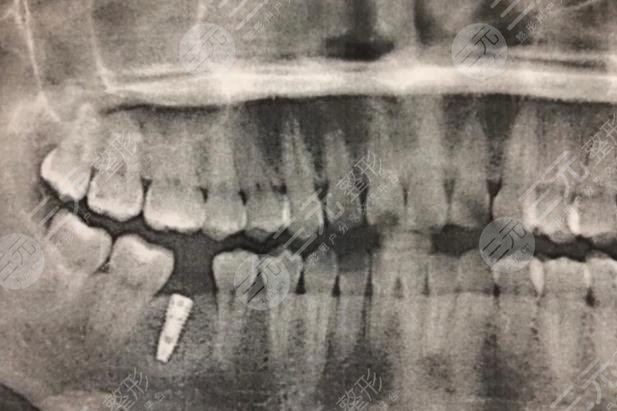

One of my back teeth was accidentally knocked out during a meal, probably because my previous teeth were not very good, resulting in a small stimulation that made my teeth fall out, and then for a period of time, I didn't care much about this lost tooth, knowing that slowly the surrounding teeth began to hurt, and then I went to the dental hospital, planning to check it out.

After the examination at the hospital, the doctor told me that the place where the tooth was lost was not cleaned properly, resulting in inflammation of the surrounding teeth, and then the doctor told me that I should fill the tooth, and then gave me a few plans, after listening to his introduction, I chose dental implants, which are better looking than ordinary dentures, and the sense of use is better, the color is more natural, and there is no difference from my own teeth.

Then the whole process of dental implants was done for more than 3 months, and there was a period of recovery in the middle, but fortunately, the results were relatively good, just like the introduction, and it was completely impossible to see that it was an implanted tooth.